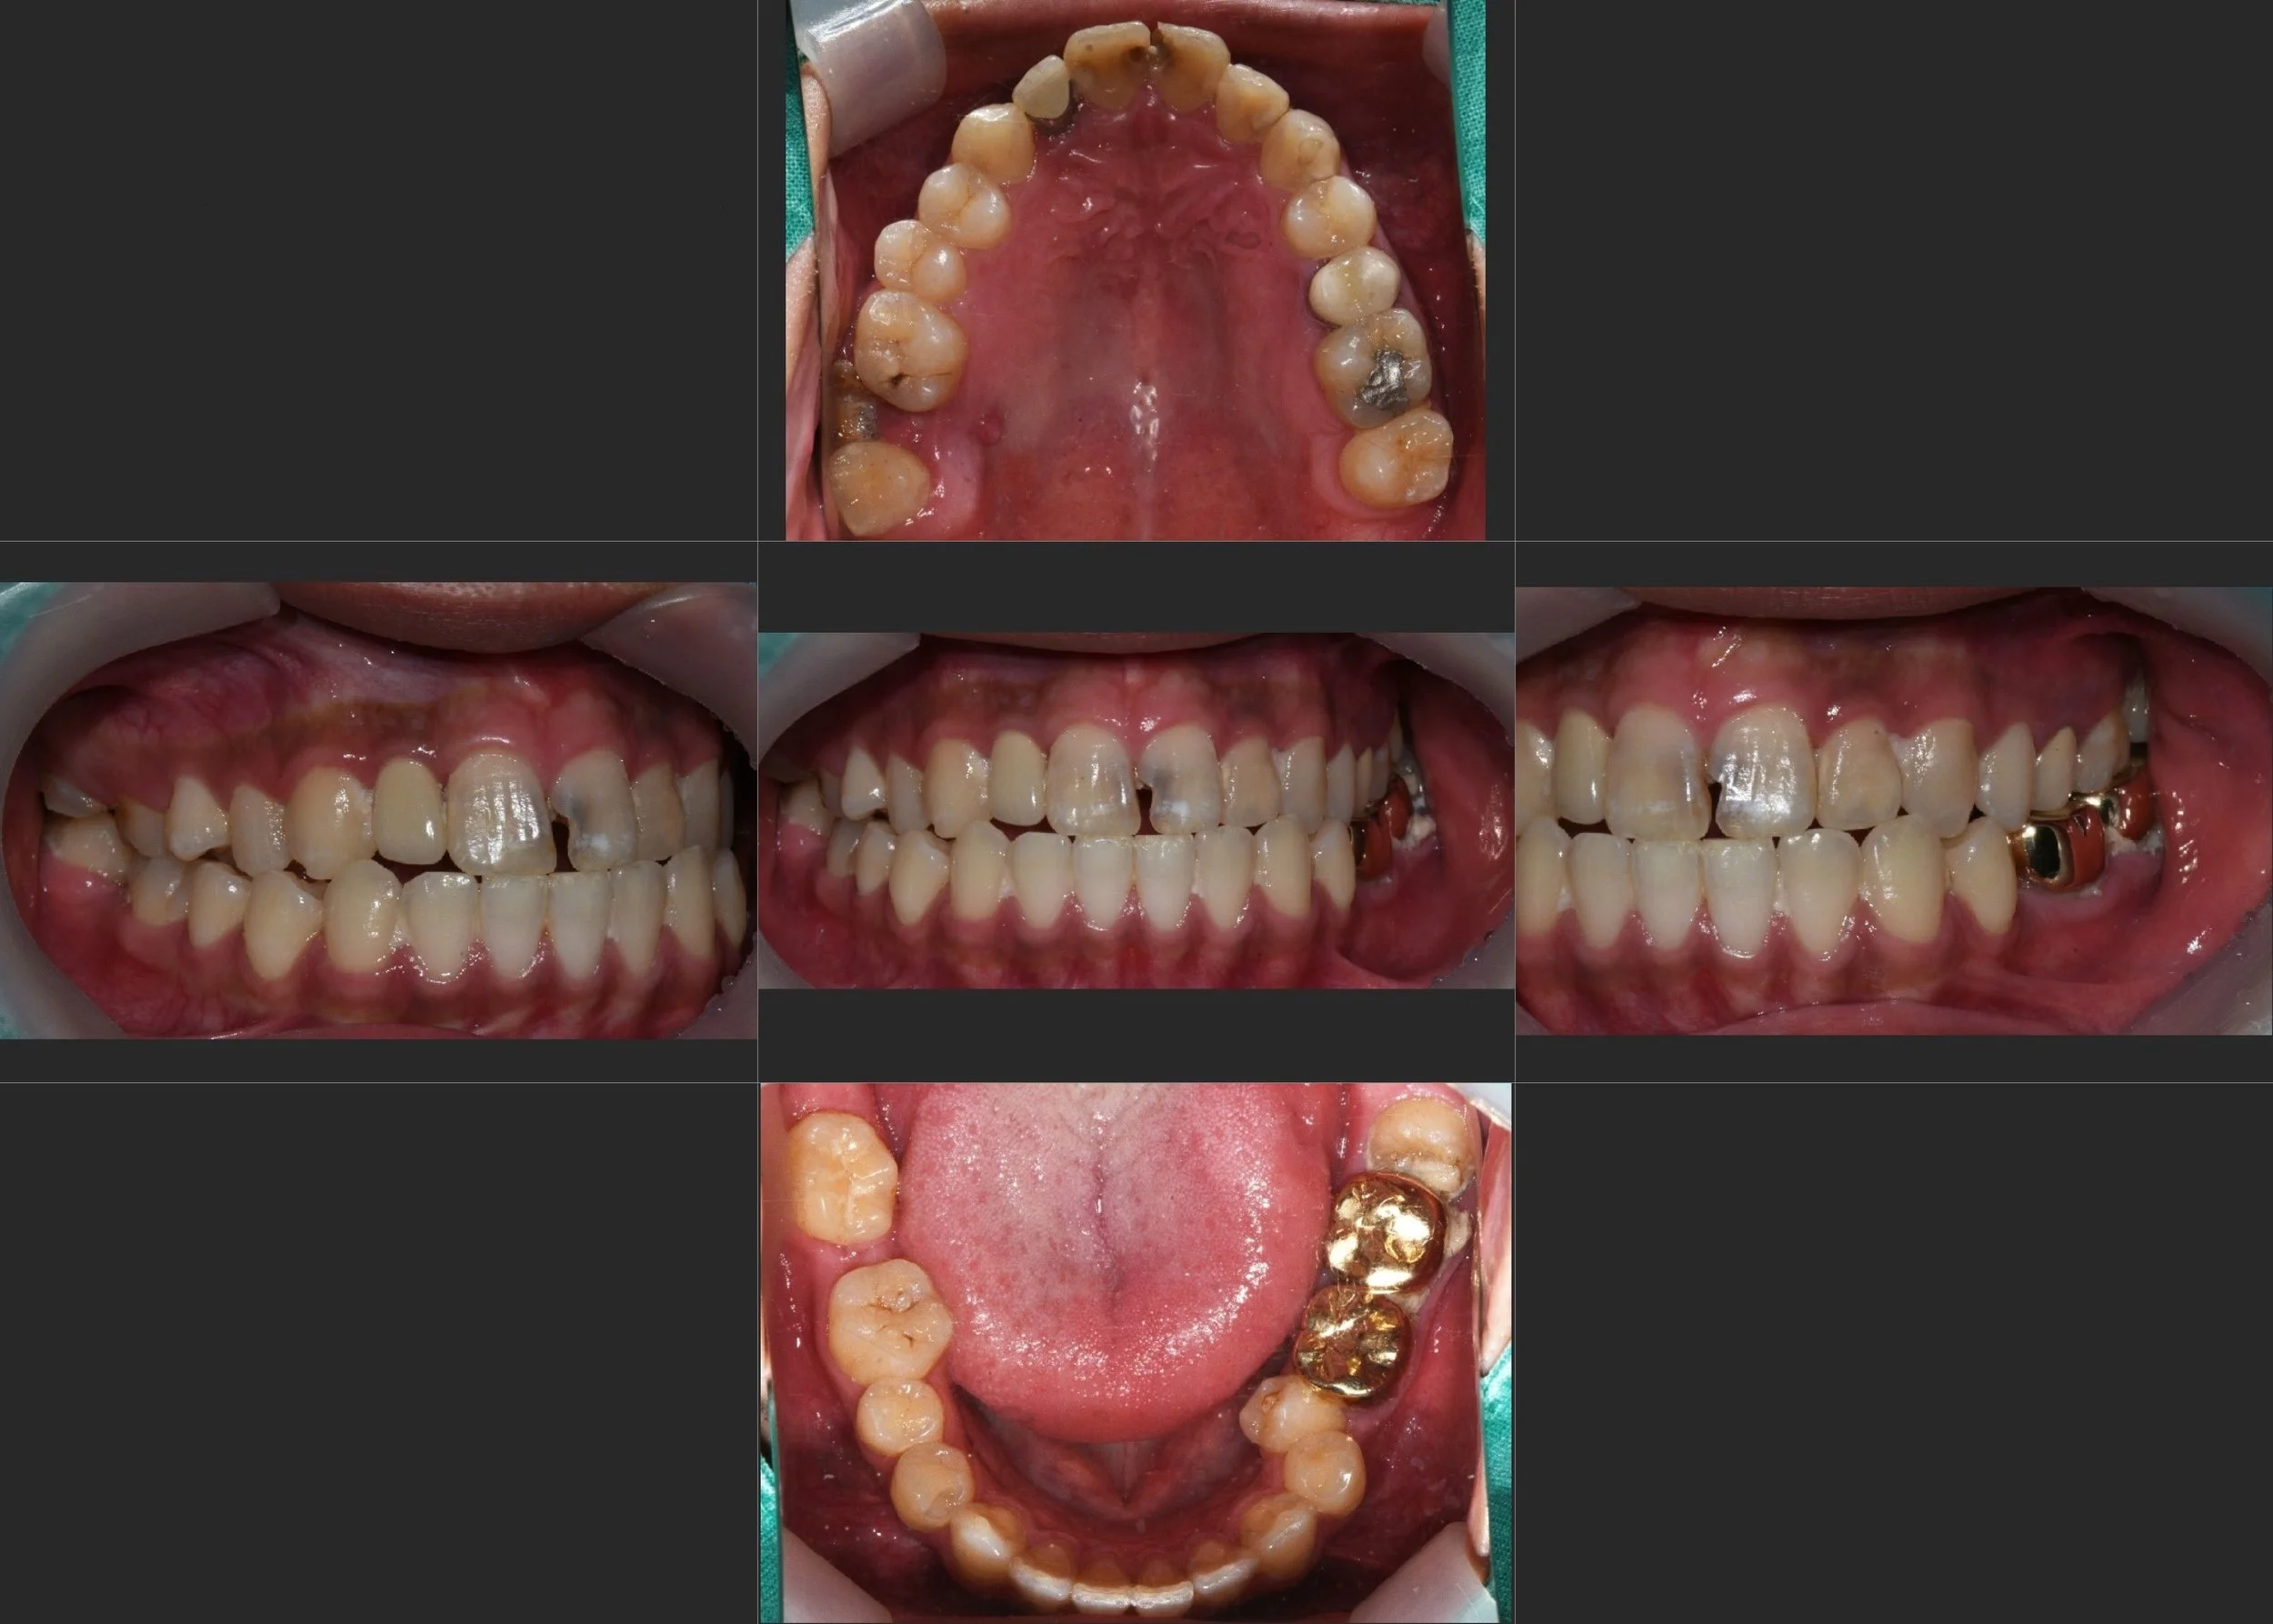

INTRA ORAL - BEFORE

A male patient in his 20s presented with extensive dental caries across multiple teeth and a significantly compromised occlusal relationship. The primary clinical concerns were:

• Generalized Rampant Caries: Multiple teeth required urgent restorative and endodontic intervention.

• Mandibular Deviation & Midline Shift: The patient exhibited a noticeable shift in the dental midline and mandibular deviation, leading to both functional instability and aesthetic disharmony.